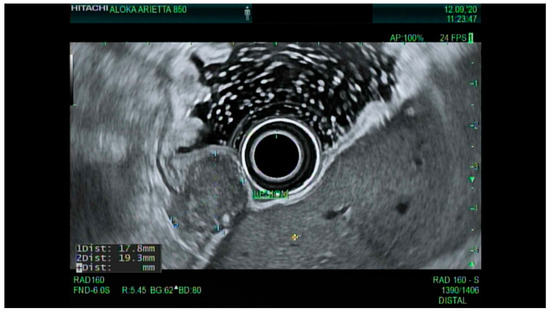

4.3. Endoscopic Ultrasound in Staging of Gastric Cancer